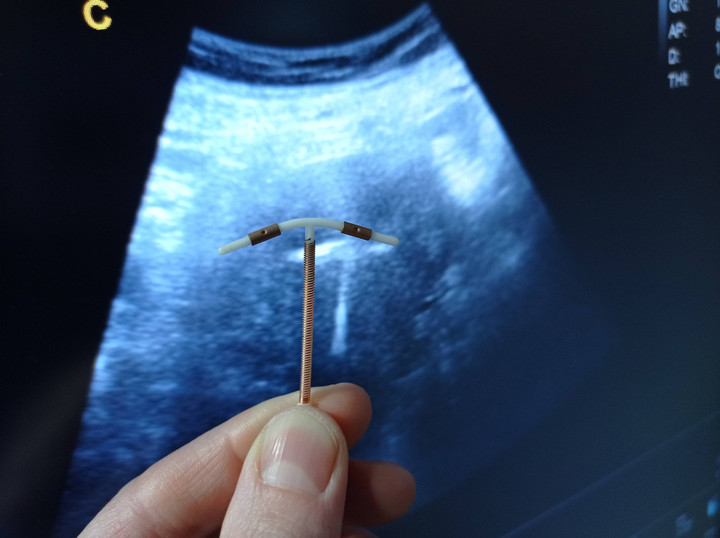

Alat kontrasepsi atau KB IUD (Intrauterine Device) Copper T menjadi salah satu alat kontrasepsi yang dinilai efektif untuk mengatur jarak kehamilan. Jenis IUD copper T merupakan KB non-hormonal dan penggunaanya bisa mencapai 5-8 tahun dengan kontrol biasanya 30 hari usai pemasangan dan setiap tahun.

Dokter Spesialis Kebidanan dan Kandungan, dr. Andrew Yurius Christian, SpOG menjelaskan cara kerja IUD Copper T. Cara kerja copper T ada 2. Yang pertama, saat pre-fertilisasi, ion tembaga akan mengganggu pergerakan dan merusak sperma.

Setelah itu, saat post-fertilisasi, ion tembaga mengakibatkan peradangan pada dinding endometrium sehingga membuat embrio tidak dapat menempel untuk berkembang.